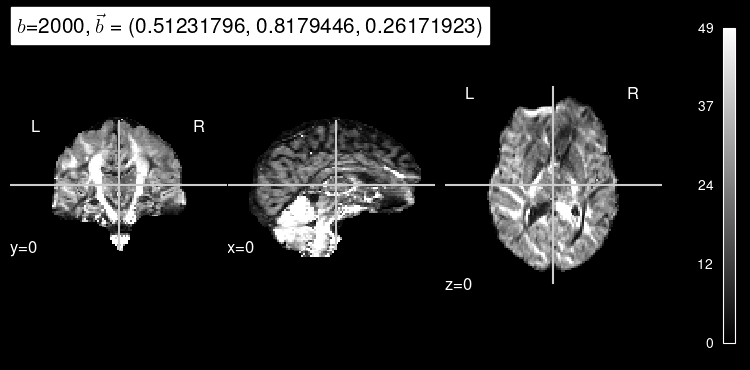

Now, the predicted map for the particular b gradient looks much closer to the original:

plot_dwi(predicted, dmri_dataset.affine, gradient=test_b, black_bg=True);

Here’s the original DW map, for reference: